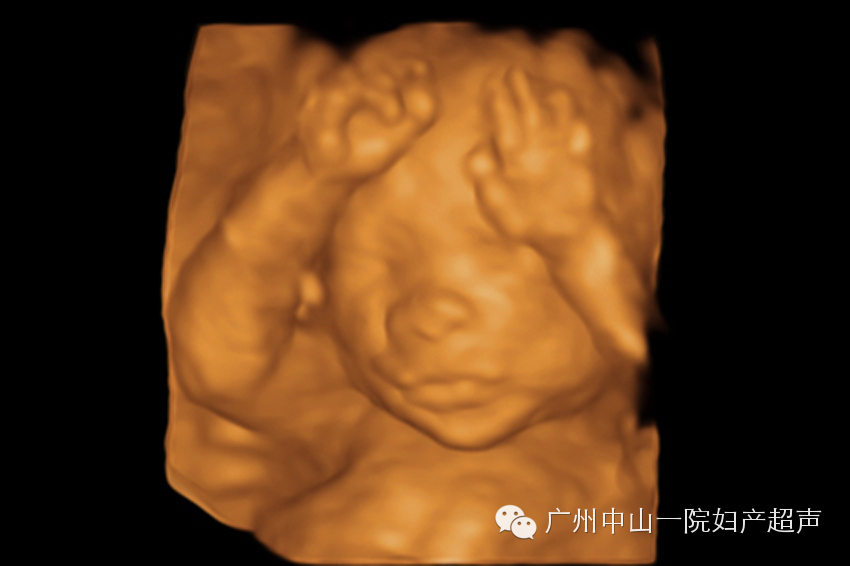

此次检查最重要目的是观察胎儿全身各系统结构是否存在畸形。这个时候,胎儿已经比较大了,三维超声无法获取胎儿的全身照,道理就如同相机无法近距离拍摄大物体的全貌一样。我们通常只建立宝宝的面部三维图像,满足准妈妈们求貌若渴的心情。如果条件良好,宝宝的五官可以清晰的呈现出来,嘴唇、鼻子、眼睛(通常是闭着的)甚至人中都可以一一分辨。对于我来说,工作中最开心的部分就是看着准妈妈们对着宝宝的照片评头论足,感受超声技术的神奇和母子之间的情感交融。